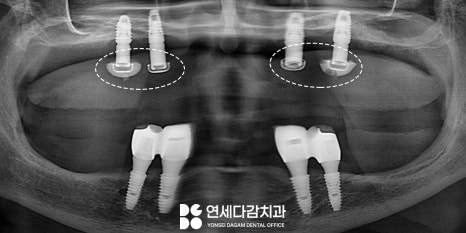

예를 들어 로케이터 타입의 오버덴쳐,

흔히 똑딱이 틀니라고 불리는 것을

사용 중이라면,

오버덴쳐는 임플란트와 연결되는

특수한 구조를 가지고 있으므로

수리 과정에서 이 부분에는 문제가 없는지

확인하는 과정이 필요합니다.